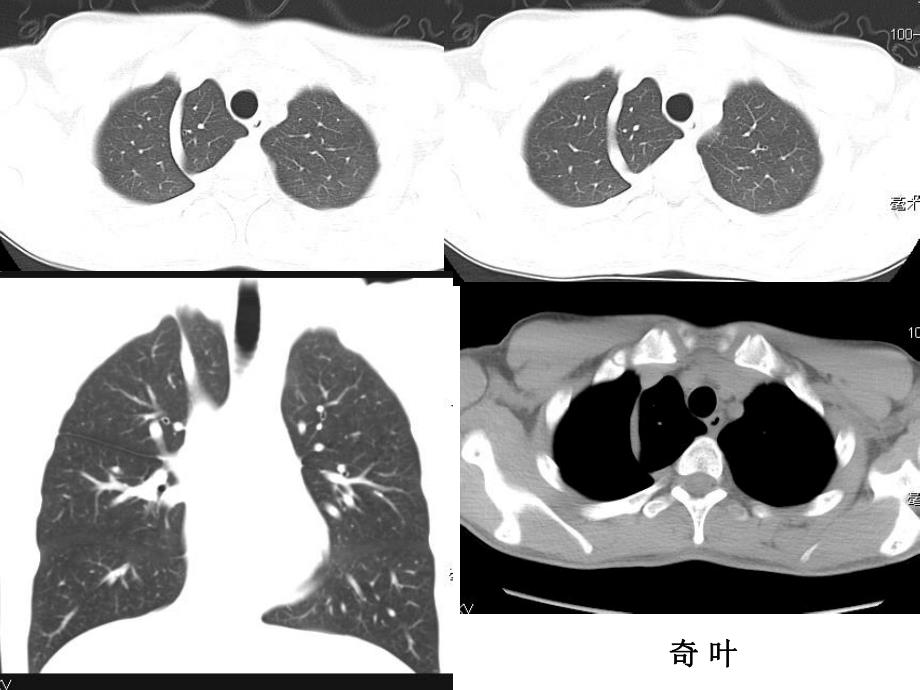

呼吸系统及纵隔呼吸系统及纵隔奇奇 叶叶大叶性肺炎 肺大疱 肺炎治疗后复查 慢性支气管炎、肺气肿 心包积液 支气管扩张 支气管扩张 支气管扩张病例1:鸽子肺CT:27088病例2少量胸腔积液的CT和MR周围型肺癌(小细胞癌)中心型肺癌正常上叶舌段支气管肺上沟癌MR:050668肺挫伤肋骨骨折,胸腔积液,肺不张皮下积气升主动脉瘤 主动脉夹层